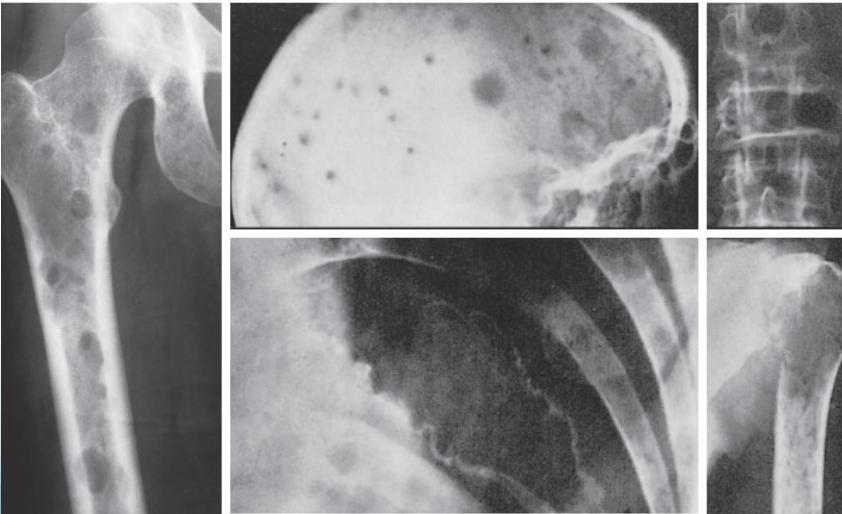

Radiological Features

- X-ray:

- Multiple punched-out lesions

- Osteoporosis & Vertebral compression fracture:

- If both present in a male >45: ? Myeloma

- Common sites:

- Skull, Prox. Femur, vertebrae

- Radiolucency and sclerosis

- Poorly defined margins

- Extends into soft tissue

- Periosteal reaction:

- Sunburst (sun-ray) appearance

- Codman’s triangle

Source: Orthopedic Radiology. A Greenspan. Lippincott-Raven